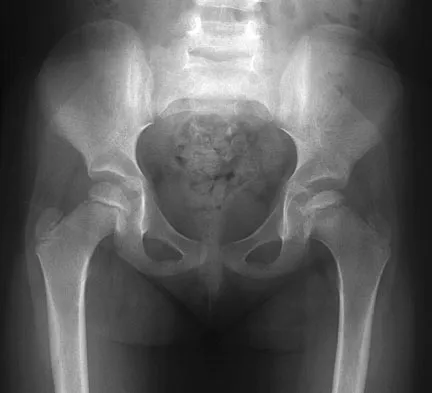

Master ABOS/OITE pediatric orthopedic boards with Set 4 practice MCQs. Covers high-yield topics like Developm…

Master AAOS & ABOS Ortho Board exams with Set 3 practice MCQs. Covers pediatric femur fractures, developmenta…

Master AAOS, ABOS, and OITE exams with practice MCQs from Set 2, covering pediatric hip disorders like DDH & …

Prepare for AAOS, ABOS, and OITE with Pediatric Orthopedics MCQs (Set 1). Test your knowledge on common pedia…